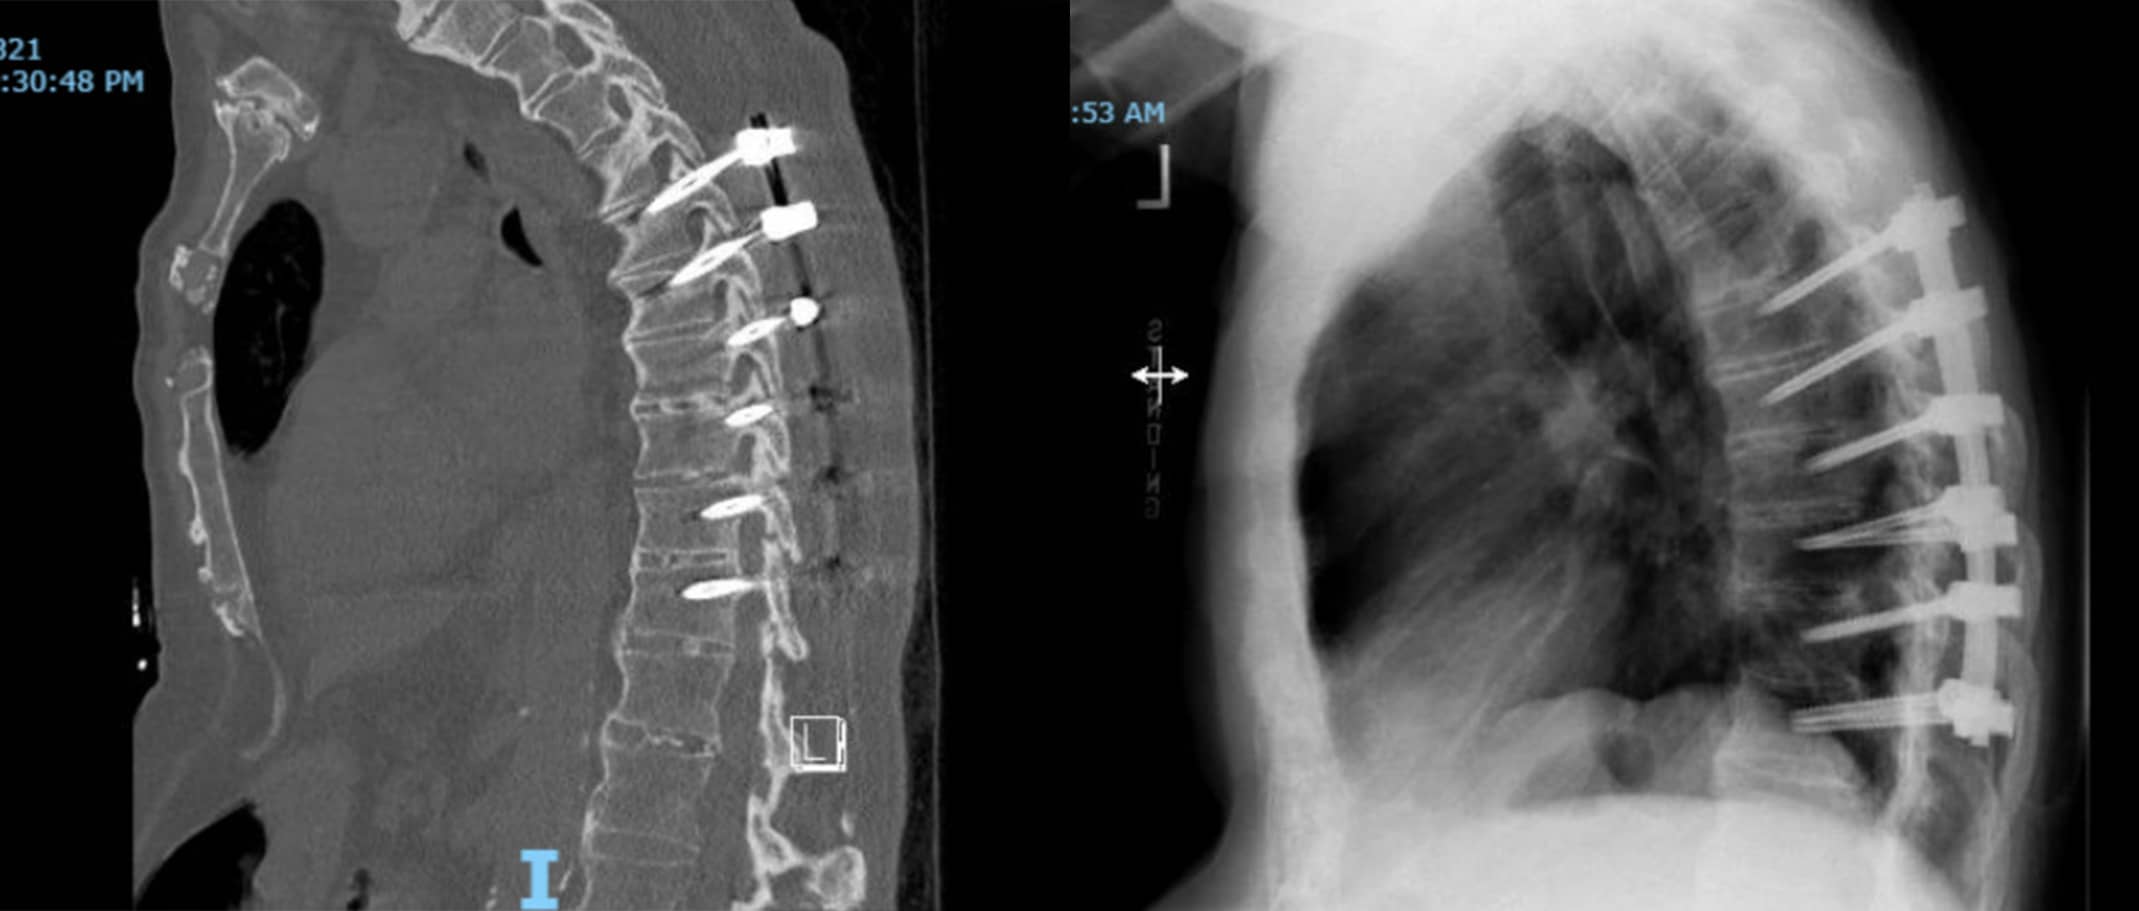

CT Scan Showing Ankylosing Spondylitis

CT scan of a patient with ankylosing spondylitis, taken before fusion surgery.

CT Scan and X-Ray After Fusion Surgery for Ankylosing Spondylitis

CT scan (Left) and X-ray (Right) of the above patient after fusion surgery.